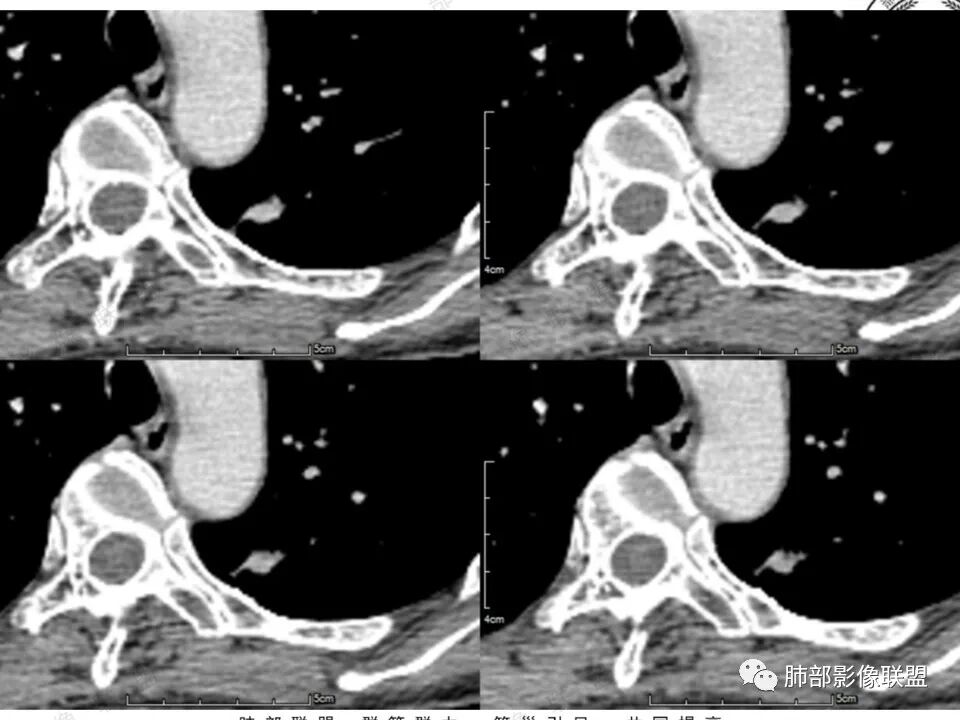

左肺上叶尖后段实性结节,边缘有清晰磨玻璃,胸膜有牵拉凹陷,明显强化,CT值超过主动脉,考虑血管畸形(周围磨玻璃可能是出血),鉴别IAC(影像表现符合,强化不符)

41岁女性,左肺上叶不规则结节,边缘见似清非清的磨玻璃影,叶间裂牵拉。整体病灶边缘平直,强化明显。另左上叶外侧尚有一磨玻璃结节(蘑菇兄弟?),考虑炎性肉芽肿可能性大。强化太明显让人很纠结,会不会存在CD,但边缘又有磨玻璃影;腺癌、结核、隐球都没有见过强化这么明显的,强化程度与主动脉基本一致,不会是动静脉畸形吧。

没意见:

强化太猛,血管畸形?边缘磨玻璃区,腺癌?

4.本例结节强化程度明显低于主动脉,也缺乏血管畸形的典型的迂曲结构,血管畸形可能性不大。